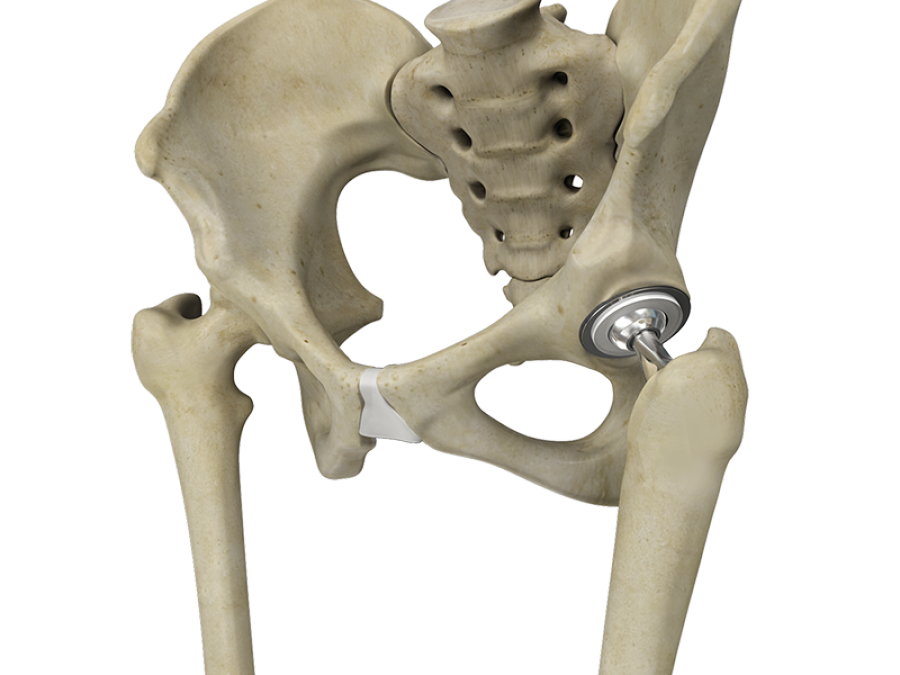

Artificial thigh jointFor prosthetics, two types of prostheses are used: a total endoprosthesis (TEP) and an articular prosthesis (SSP).

In total endoprosthetics due to the traditional form of the prosthesis, removal (resection) of the neck and the head of the hip joint with subsequent destruction of the bone marrow of the femur is necessary for implantation of the prosthetic foot with the head and the corresponding cavity.

An undeniable advantage in the prosthetic repair of the ICON articular surface is that only the damaged surface of the femoral head is removed by grinding and grinding.

The ideal match with the size and shape of the hip joint joint prosthesis determines the following benefits:

Preserved natural geometric relationships, which avoids the difference in the length of the lower limbs.

As a result of the preservation of anatomical structures, natural sensations of movement are also preserved.

The load exerted on the bone remains unchanged, which preserves the normal structure of bone tissue and prevents the development of osteoporosis.

The metal-metal friction pair of the corresponding human anatomy provides for an ideal joint stability.

The anatomical dimensions of the cap part of the prosthesis determine the physiological volume of movement in the joint.

Components of an ICON joint surface prosthesis